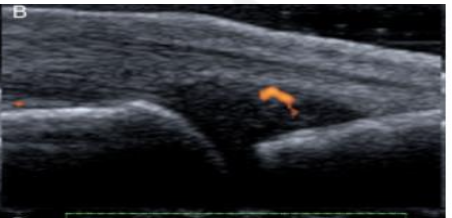

Grade this

B: grade 1 (up to 3 single signals — 1 confluent + 2 single — 2 confluent)

Minimal synovial hypertrophy up to the imaginary horizontal line connecting 2 joints; Power Doppler up to 3 single signals — 1 confluent + 2 single — 2 confluent

Grade 1: minimal